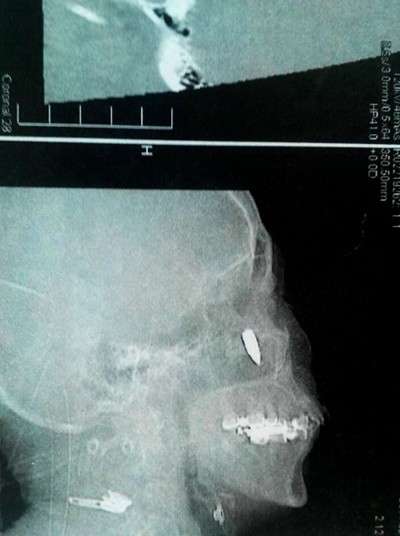

X光显示19厘米长的铁丝穿过了中国广州一名男子的头部。据目击者回忆:“他当时在修葺雨篷,突然从梯子上掉了下来,他在地上呆了几分钟说他没事,但是他回过头来我就看到一根铁丝从他的头里伸了出来。他赶紧跑去医院接受治疗。手术持续了5个小时,取出了一根19厘米长的铁丝,其中有14厘米扎在他的脑袋里。医生说,铁丝距离他的静脉只有2毫米而距离颈动脉只有5毫米,任何血管的破裂都会造成患者当场死亡。他真的十分幸运。铁丝一直戳到他的后脑壳。